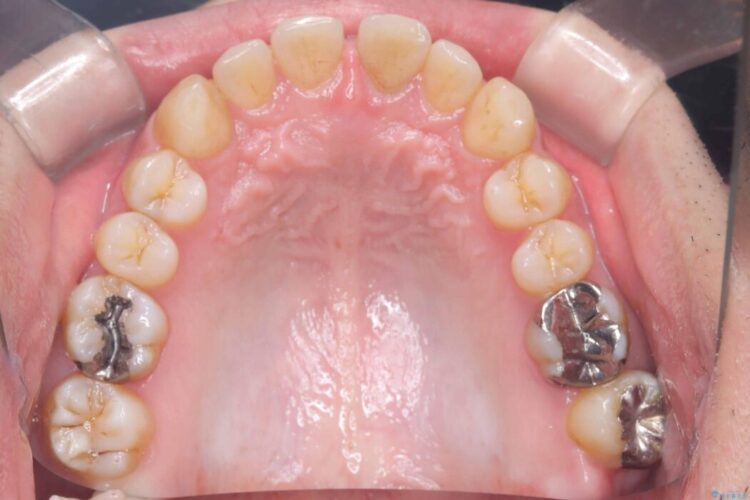

正中離開・叢生のほかに、上下の奥歯が全く咬み合わないシザーズバイトの状態も認められました。

精密検査の結果、非抜歯でインビザラインによる治療が可能と判断し、治療を行うこととしました。